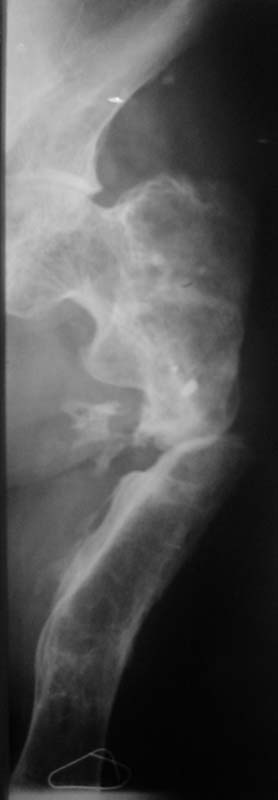

Судя по представленному снимку, есть 3 деформации – Варусная в области ложного сустава - 70°, Вальгусная - 35° в средней трети бедра, и ещё одна вальгусная 8° в области дистального метаэпифиза бедренной кости. Если бы пациент попал ко мне, я сделал бы трилокальный остеосинтез – Открытый погружной копрессионный в области ложного сустава, остеотоми на вершине деформации средней трети бедра для удлинения и коррекции деформации и коррегирующую остеотомию через верхний край мыщелков бедренной кости. Для оппонентов такой тактики сразу оговорюсь, что коррекция анатомической и механической оси при наличии срастающегося ложного сустава критична для профилактики рефрактуры.

Хотя я полагаю, что открытый билокальный остеосинтез тоже может иметь место в данной ситуации, при котором откратый погружной остеосинтез ложного сустава будет сочетаться с остеотомией средней трети бедра для коррекции механической оси (я подчёркиваю механической) бедра. Для этого надо произвести перерасчёты в конце удлинения по снимкам бедра на всю длину.

По поводу операции на ложном суставе: необходимо убрать все фиброзные ткани между концами отломков, вскрыть каналы проксимального и дисталного отломков для улучшения кровообращения в месте сращения, проксимальному отломку придать овальную форму вершиной вверх и погрузить дистальный отломок в проксимальный на пол сантиметра, это необходимо для увеличения площади контакта между отломками. Будьте осторожны с одномоментным устранением деформации! Следите за пульсом на дистальной части ноги. Не забывайте, что аппарат Илизарова позволяет устранить деформацию постепенно, что более физиологично для мягких тканей.

Компановка аппарата: Маленькая дуга с 4-5 полустержнями типа Шанца, 6 мм диаметре , желательно конусовидные (один из них обязательно должен быть проведён в малый вертел – даёт очень прочную фиксацию) 2 – в шейку бедра.

Если укорочение большое, не обязательно проводить лечение в один этап. Можно на первом этапе срастить ложный сустав и удлинить частично, а на втором доудлинить и сравнять длину ног.